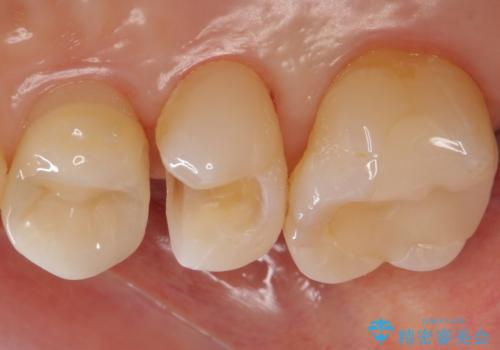

- 銀の詰め物を白くしたいとのことで来院されました。

セラミックインレーでの治療を行いました。

残る歯の厚みが確保されている場合はインレーでの修復が可能です。